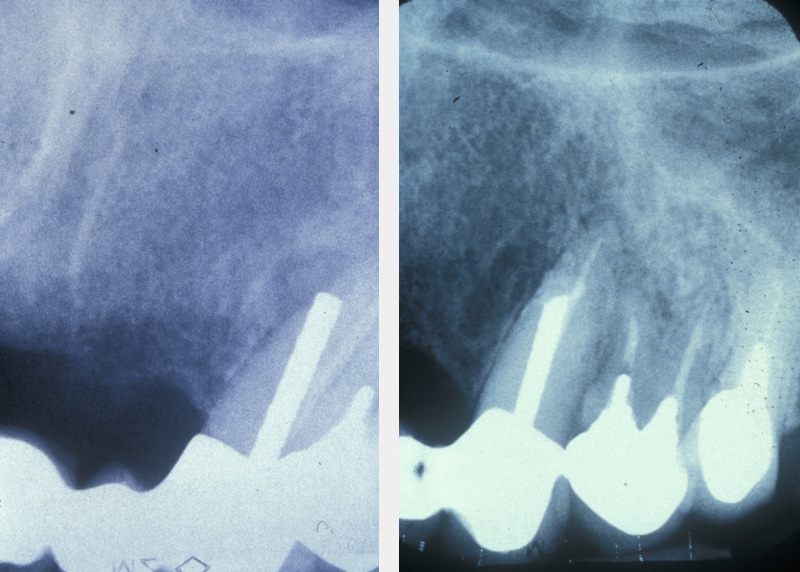

A medical history, clinical examination, and radiological examination should be performed when surgical endodontic treatment is being considered. Where applicable, previous conventional endodontic treatment (root canal treatment) is also assessed and a decision made on its effectiveness. Local anatomical factors, such as the proximity of the surgical area to the maxillary sinus (cavity above the upper jaw) or neurovascular bundles (important nerve and blood vessel structures) need to be taken into account, as does the feasibility of surgery. Figure 1 gives an example where periapical surgery was the preferable option over conventional treatment.

Once endodontic surgery has been performed, it should be assessed after at least one year. Success is indicated by:

- absence of symptoms such as pain and swelling;

- no sinus tract (abnormal draining channel);

- no loss of function;

- satisfactory soft tissue healing;

- X-ray radiographic evidence of bony infill at the surgical site.

Figure 6 depicts the appearance one year after a surgical endodontics intervention. Long-term follow up is based on personal protocol after one year.